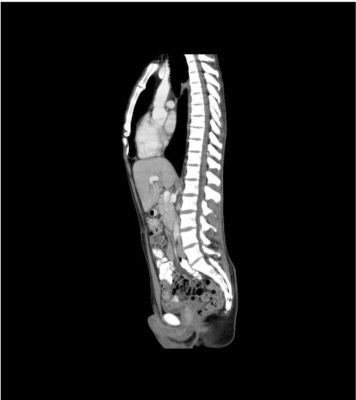

This phantom simulates a contrast medium-enhanced abdomen and pelvis in the portal venous phase. It covers the second thoracic vertebra to the perineum. It has iliac lymph node masses on the right side.

The phantom provides a detailed and realistic simulation of soft and bone tissue. Air voids including those of the lungs are filled with a cellulose-polymer composite of approx. -160 HU.

- Realistic simulation of vasculature, bone and soft tissues, including the lungs, heart, liver, gallbladder, pancreas, spleen, adrenals, kidneys, stomach, small intestine, colon, bladder and prostate.

- External iliac lymph node masses on the right side.